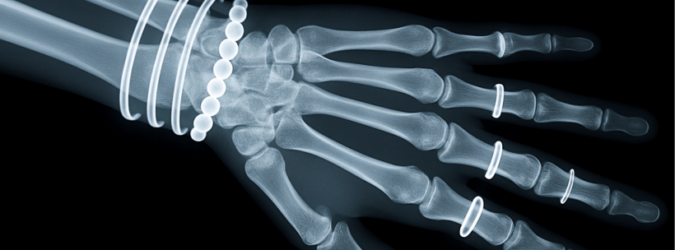

La prima radiografia della storia venne realizzata chiedendo alla moglie Berta di appoggiare la mano su una lastra fotografica. Dopo quindici minuti di esposizione, apparvero chiaramente le ossa della mano e l’anello nuziale: un’immagine destinata a diventare simbolo della medicina moderna.

Il 23 gennaio 1896 Röntgen presentò ufficialmente la sua scoperta davanti alla Physikalisch-Medizinische Gesellschaft di Würzburg, eseguendo dal vivo una radiografia della mano dell’anatomista Rudolf Albert von Kölliker. Fu la prima dimostrazione pubblica di una radiografia, destinata a segnare un punto di svolta irreversibile.